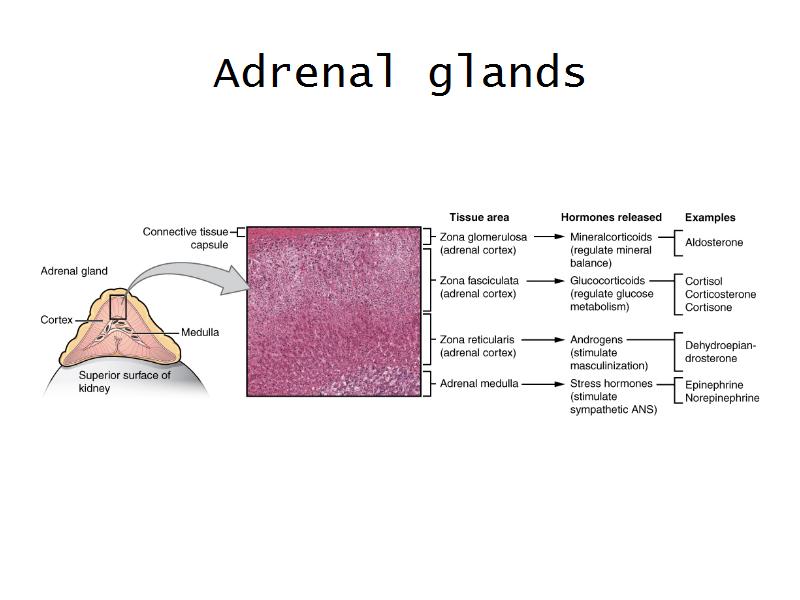

Adrenal glands

Capsule

Cortex - how many zones?

Medulla

Hormones of each?